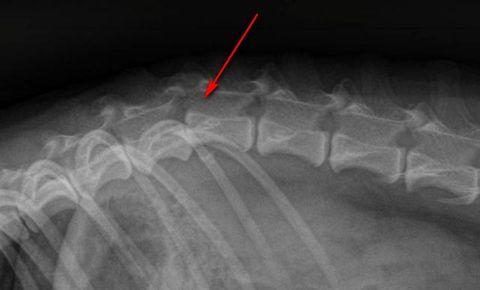

- Рентгенография.

- Рентгенография грудной клетки и позвоночника. С помощью рентгена специалист выявляет дегенеративно-дистрофические признаки, характерные для хондроза, — деформацию и истончение межпозвонковых дисков. Также рентгенограмма дает возможность исключить патологии легких.